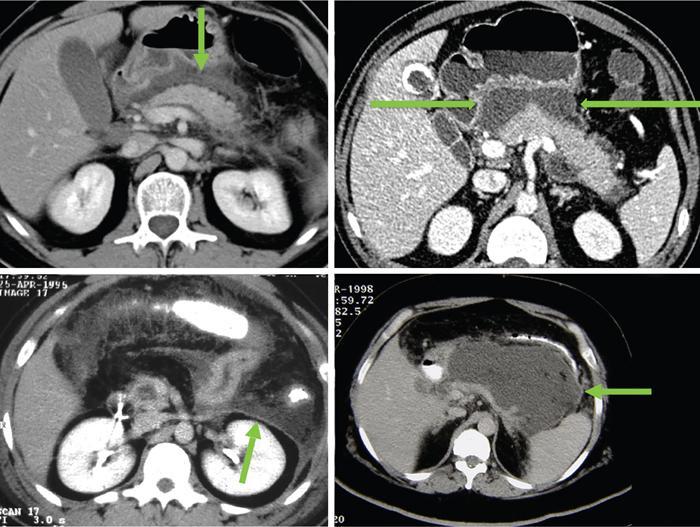

Anirudh Kohli Acute pancreatitis is one of the most dreaded diseases to afflict mankind, in view of its high morbidity and mortality. The single most important factor in reducing the morbidity and mortality of this condition over the last many years has been the role of computed tomography (CT). The incidence of acute pancreatitis is rising especially due to an increasing incidence of gallstones, obesity, as well as an ageing population. Pancreatitis occurs due to a chain of events triggered by a temporary/permanent pancreatic duct obstruction. This leads to activation and release of pancreatic enzymes into pancreatic interstitium and peripancreatic tissues leading to severe auto digestion and necrosis of pancreas and adjacent tissues. Systemically there is release of inflammatory mediators known as cytokines. Tumour necrosis factor is a cytokine which is toxic to acinar cells. These cytokines activate and intensify the inflammatory cascade that may ultimately culminate in multiorgan failure. Clinically severe acute pancreatitis is characterized by two phases, an early phase and a late phase. The early phase is dominated by the systemic effects of release of inflammatory mediators such as cytokines – termed as systemic inflammatory response syndrome (SIRS). Usually there is associated variable multiorgan dysfunction/failure. This phase lasts for a week. When the multiorgan failure lasts 2 days it is termed as mild, multiorgan failure lasting more than 48 hours is considered severe. There is no correlation between the clinical severity of pancreatitis and morphological changes in this early stage. In view of this CT scan is not of much utility during this phase, unless complications are suspected. The later phase is dominated by effects of local complications due to pancreatic/peripancreatic necrosis. Mortality follows this biphasic pattern in early weeks from the systemic effects of multiorgan failure and in later weeks due to local effects, for example infection of necrotic pancreatic/peripancreatic tissues superimposed by organ failure. The Clinical diagnosis of acute pancreatitis requires two of the following three features: If the first two findings are present without any significant SIRS then CT is not required. Acute pancreatitis is a complex disease with a wide variation in the presentation and outcome, ranging from asymptomatic with only biochemical alterations to a fatal outcome. In fact acute pancreatitis is a dynamic disease with continuously evolving appearances on imaging. There are two distinct forms of acute pancreatitis – interstitial oedematous pancreatitis and acute necrotising pancreatitis. Interstitial oedematous pancreatitis is a condition where there is only mild swelling of the pancreas with loss of normal lobulations and a diffuse decrease in attenuation of the pancreas. There may be heterogeneity of the pancreatic parenchyma due to varying degrees of interstitial oedema. This form of pancreatitis runs a mild course and rarely progresses to acute necrotising pancreatitis with its associated complications. In a third of these cases the pancreas may reveal no abnormality on a CT scan. The inflammatory changes may be restricted to the pancreas or extend into the peripancreatic regions. The inflammation in the peripancreatic regions manifests as acute pancreatic effusions. If there is peripancreatic fat necrosis with an oedematous pancreatic gland it is termed as acute necrotising pancreatitis (Figs. 9.17.1–9.17.2). Acute pancreatic fluid collections are enzyme-rich pancreatic juice collections seen in about 40% of patients with acute pancreatitis. The fluid collections occur due to exudation of pancreatic juices into the interstitium of the pancreas and subsequently leakage into the surrounding tissue spaces. These fluid collections are localized only by the anatomic space in which they collect. As the exudative process continues, the parietal peritoneum overlying the pancreas may be disrupted with the inflammatory fluid entering the lesser sac. From the lesser sac the fluid can enter the peritoneal cavity via the foramen of Winslow or by dissecting the peritoneum along the anterior surface of the lesser sac. Posterior extension of the fluid collection in the anterior pararenal space may occur into a potential space between the laminae of the posterior pararenal fascia. Rarely there may be involvement of the perirenal and posterior pararenal spaces. Other pathways of dissection are along the gastrohepatic, gastrosplenic and gastrocolic ligaments. Fluid may dissect along the root of the mesentery into the transverse mesocolon. Collections may extend around the caecum, ascending colon, descending colon and into the lumbar, pelvic and inguinal regions. Large fluid collections may dissect superiorly into the mediastinum or pericardial space. The quantity of fluid in these effusions is variable and can range from a small amount to large quantities (Fig. 9.17.3). Of these collections, 50% resolve spontaneously; the remainder may evolve after 4–6 weeks into pseudocysts. As the collections age, they tend to get localized and walled off, often developing an enhancing wall. A collection should be termed a pseudocyst only when a definite capsule develops and the collection has been static for at least 4–6 weeks. The risk of complications such as rupture, infection and haemorrhage increases with the age of the collection. Large collections of fluid are usually associated with a lesser degree of pancreatic necrosis as compared to extensive pancreatic necrosis associated with a lesser amount of fluid collection. Acute necrotising pancreatitis is a fulminant form of pancreatitis in which there is necrosis of the pancreas, that is nonviable pancreatic tissue. A contrast-enhanced CT is essential as it is the ideal means to demonstrate necrosis as well as to determine the extent of necrosis. These areas of nonviable pancreatic tissue do not enhance as compared to viable pancreatic tissue, which demonstrate significant enhancement. The extent of pancreatic necrosis has been found to correlate extremely well with the extent of necrosis found at surgery. The size, location and extent of pancreatic necrosis are very variable. These areas may be diffuse or focal, small in size to complete glandular involvement. These necrotic areas have a very important bearing on the course of pancreatitis, as they are liable to undergo secondary infection and form pancreatic sepsis. In addition, the more extensive the pancreatic necrosis the greater is the morbidity and mortality. Patients with no pancreatic necrosis have been found to have a 0% mortality and a 6% complication rate, whereas patients with pancreatic necrosis have a 23% mortality rate and an 82% complication rate. A variety of laboratory tests are available to detect pancreatic necrosis, such as a rise in the serum methemalbumin, quantitative estimation of C-reactive protein and urinary trypsinogen-activated peptide. CECT is still the most accurate modality to detect pancreatic necrosis. Pancreatic necrosis may be seen in the pancreas only, peripancreatic tissues also or only in the peripancreatic region. Isolated peripancreatic necrosis occurs due to disruption of the peripheral ductules with extravasation of activated pancreatic enzymes, may be seen in up to 20% of patients who require operative/interventional management of their necrotising pancreatitis. These patients with only peripancreatic necrosis have a better prognosis. This essentially represents retroperitoneal fatty tissue necrosis appearing as heterogeneous areas of liquid and nonliquid components. Over time necrosis evolves and liquefies as well as the liquid component resorbs. Generally if the liquid component is 2 cm or less it will resorb, while fluid collections 5 cm or more rarely resorb. If pancreatic necrosis is not resorbed it may get walled off or with time or may become infected. Encapsulation occurs between the third and fourth weeks. It is important to differentiate sterile from infected necrosis as sterile necrosis rarely needs surgery, whereas infected necrosis requires long-term antibiotic therapy and/or some kind of imaging/surgical intervention. According to the Atlanta 2012 classification, all areas of pancreatic necrosis are termed as acute necrotic collections. This represents a combination of pancreatic/peripancreatic fat necrosis with peripancreatic effusions. On CT, there is a spectrum of findings – solid, liquid containing debris (these may be nonwalled off/partially walled off). Sonography and MRI have advantages over CT scan in demonstration if the contents are pure liquid such as acute pancreatic effusions or have some nonliquefied components such as acute necrotic collections. Pseudocysts are round or oval encapsulated fluid collections containing only liquefied components. It takes 4 weeks for the granulation tissue to develop. On CT, a pseudocyst appears as a well-defined fluid collection with a thin capsule. The most common location for pseudocysts is the lesser sac, though they may be found anywhere in the mediastinum, abdomen or pelvis as they may dissect along fascial planes, along vessels and through capsules of solid organs. Pseudocysts in the bowel, though reported, are relatively rare, as the bowel wall is a strong barrier to the effect of proteolytic pancreatic enzymes. When the contents of the pseudocyst are heterogeneous or uniformly increased in attenuation, the possibilities of infection or haemorrhage should be considered. Focal areas of increased density within the fluid collection usually indicate haemorrhage. Complicated, enlarging or symptomatic pseudocysts require percutaneous catheter or surgical drainage. Infected pseudocysts are treated by percutaneous drainage. The management of a noninfected pseudocyst is controversial. Surgical treatment is only undertaken when the wall is mature after several weeks. Large pseudocysts greater than 5 cm in size can easily be drained percutaneously using intercostal drainage tube or pigtail catheter or endoscopically via the stomach. The cure rates are reported to be 85% with percutaneous drainage, the drainage period averaging about 20 days (Figs. 9.17.4–9.17.5). Walled off necrosis – as pancreatic/peripancreatic necrosis matures and evolves, an interface develops between necrosis and adjacent fatty tissue and an enhancing thickened wall is seen, resulting in a well-defined fluid collection with necrotic debris and fat necrosis. This is the end stage in the evolution of an acute necrotic collection. It is important to differentiate a pseudocyst from walled off necrosis, as a pseudocyst requires drainage and walled off necrosis requires surgical removal (Figs. 9.17.6–9.17.9). Sepsis is a major complication of pancreatitis and is accompanied by a high incidence of mortality and a prolonged hospital stay. Pancreatic sepsis may occur following secondary infection of pancreatic and/or peripancreatic necrosis, acute pancreatic fluid collections and pseudocysts. The only specific sign to demonstrate sepsis is the presence of gas in a collection. This occurs due to secondary infection by coliform/anaerobic organisms. This sign is unfortunately not common and seen in only one-third of cases. Gas is seen in the fluid collection as very dark well-defined air attenuation bubbles. Occasionally gas may be present due to a gastrointestinal fistula or previous surgery. Fat necrosis is seen in peripancreatic collections. This should not be confused with air bubbles, which are indicative of sepsis. The differentiation is easy to understand by CT, the values of fat ranging between – 20 HU and – 80 HU, and of air being >–300 HU. Also air bubbles have well-defined margins and are homogeneously jet black, whereas fat is nonhomogeneously grey with ill-defined margins. Since the presence of air is seen only in a small percentage of patients with pancreatic sepsis, the only other means to diagnose pancreatic sepsis is by CT-guided aspiration. All sites of fluid collection, parenchymal necrosis and peripancreatic necrosis are subjected to CT-guided aspiration. This is a tedious process and requires a dedicated interventional radiologist as there are often more than 5–6 sites from which it may be necessary to obtain samples. A fresh needle and syringe are used for each site, as it is important to know which site has sepsis and which is sterile. Care is taken not to transgress the large bowel as the colon has a large number of bacteria, and transgressing it could result in colonic bacteria contaminating the CT-guided aspiration sample, with falsepositive results. Further, colonic bacteria may be inoculated into a sterile acute pancreatic fluid collection or necrosis thereby converting a sterile collection into an infected one (Fig. 9.17.10). Complications of the procedure can be pneumothorax if the pleura is transgressed, haemorrhage due to trauma to a vessel, and secondary infection. Pancreatic sepsis is treated by surgical debridement, necrosectomy and drainage through thick tubes. It is crucial from the management point of view to differentiate an abscess from infected necrosis. An abscess may be treated by percutaneous drainage, whereas infected necrosis developing in relatively solid tissue can be treated by surgical debridement alone. Imaging-guided percutaneous drainage is the first step in treating pancreatic sepsis especially patients who are very ill and cannot undergo surgery. Initially pig tail catheters were used but these are notorious to get blocked as the largest bore of a pigtail catheter is 12 F. Pancreatic sepsis contains a large amount of necrotic debris, this blocks the catheters can be cleared by flushing the catheter, but this always raises the possibility of introducing secondary infection. To circumvent this issue large-bore ICD catheters have been introduced. These range from 16 F to 30 F. A safe window is necessary, not transgressing bowel or vasculature. It is quite easy to insert these tubes percutaneously under CT. A bit of initial manipulation and force is required to pierce the abdominal musculature. These large-bore drainage tubes have been very effective unless the infected necrosis is solid with minimal liquefied contents or a safe window for placing an ICD catheter is not available. CT is also invaluable in surgical planning and in the follow-up of postoperative patients to evaluate any fresh collection and also to determine whether the drains are well sited or not (Fig. 9.17.11).